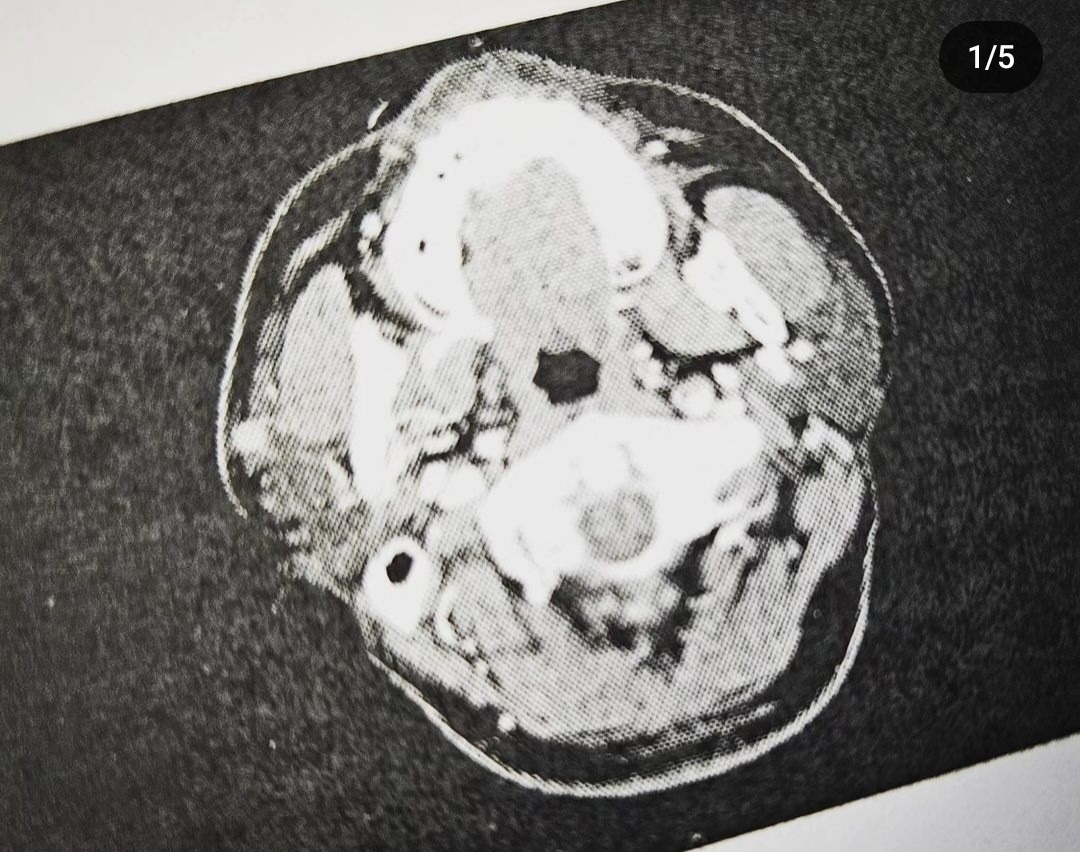

침샘암 CT와 진단명

CT 사진으로 왼쪽 하단부분의 검은 동그라미,

문제의 불청객이다.